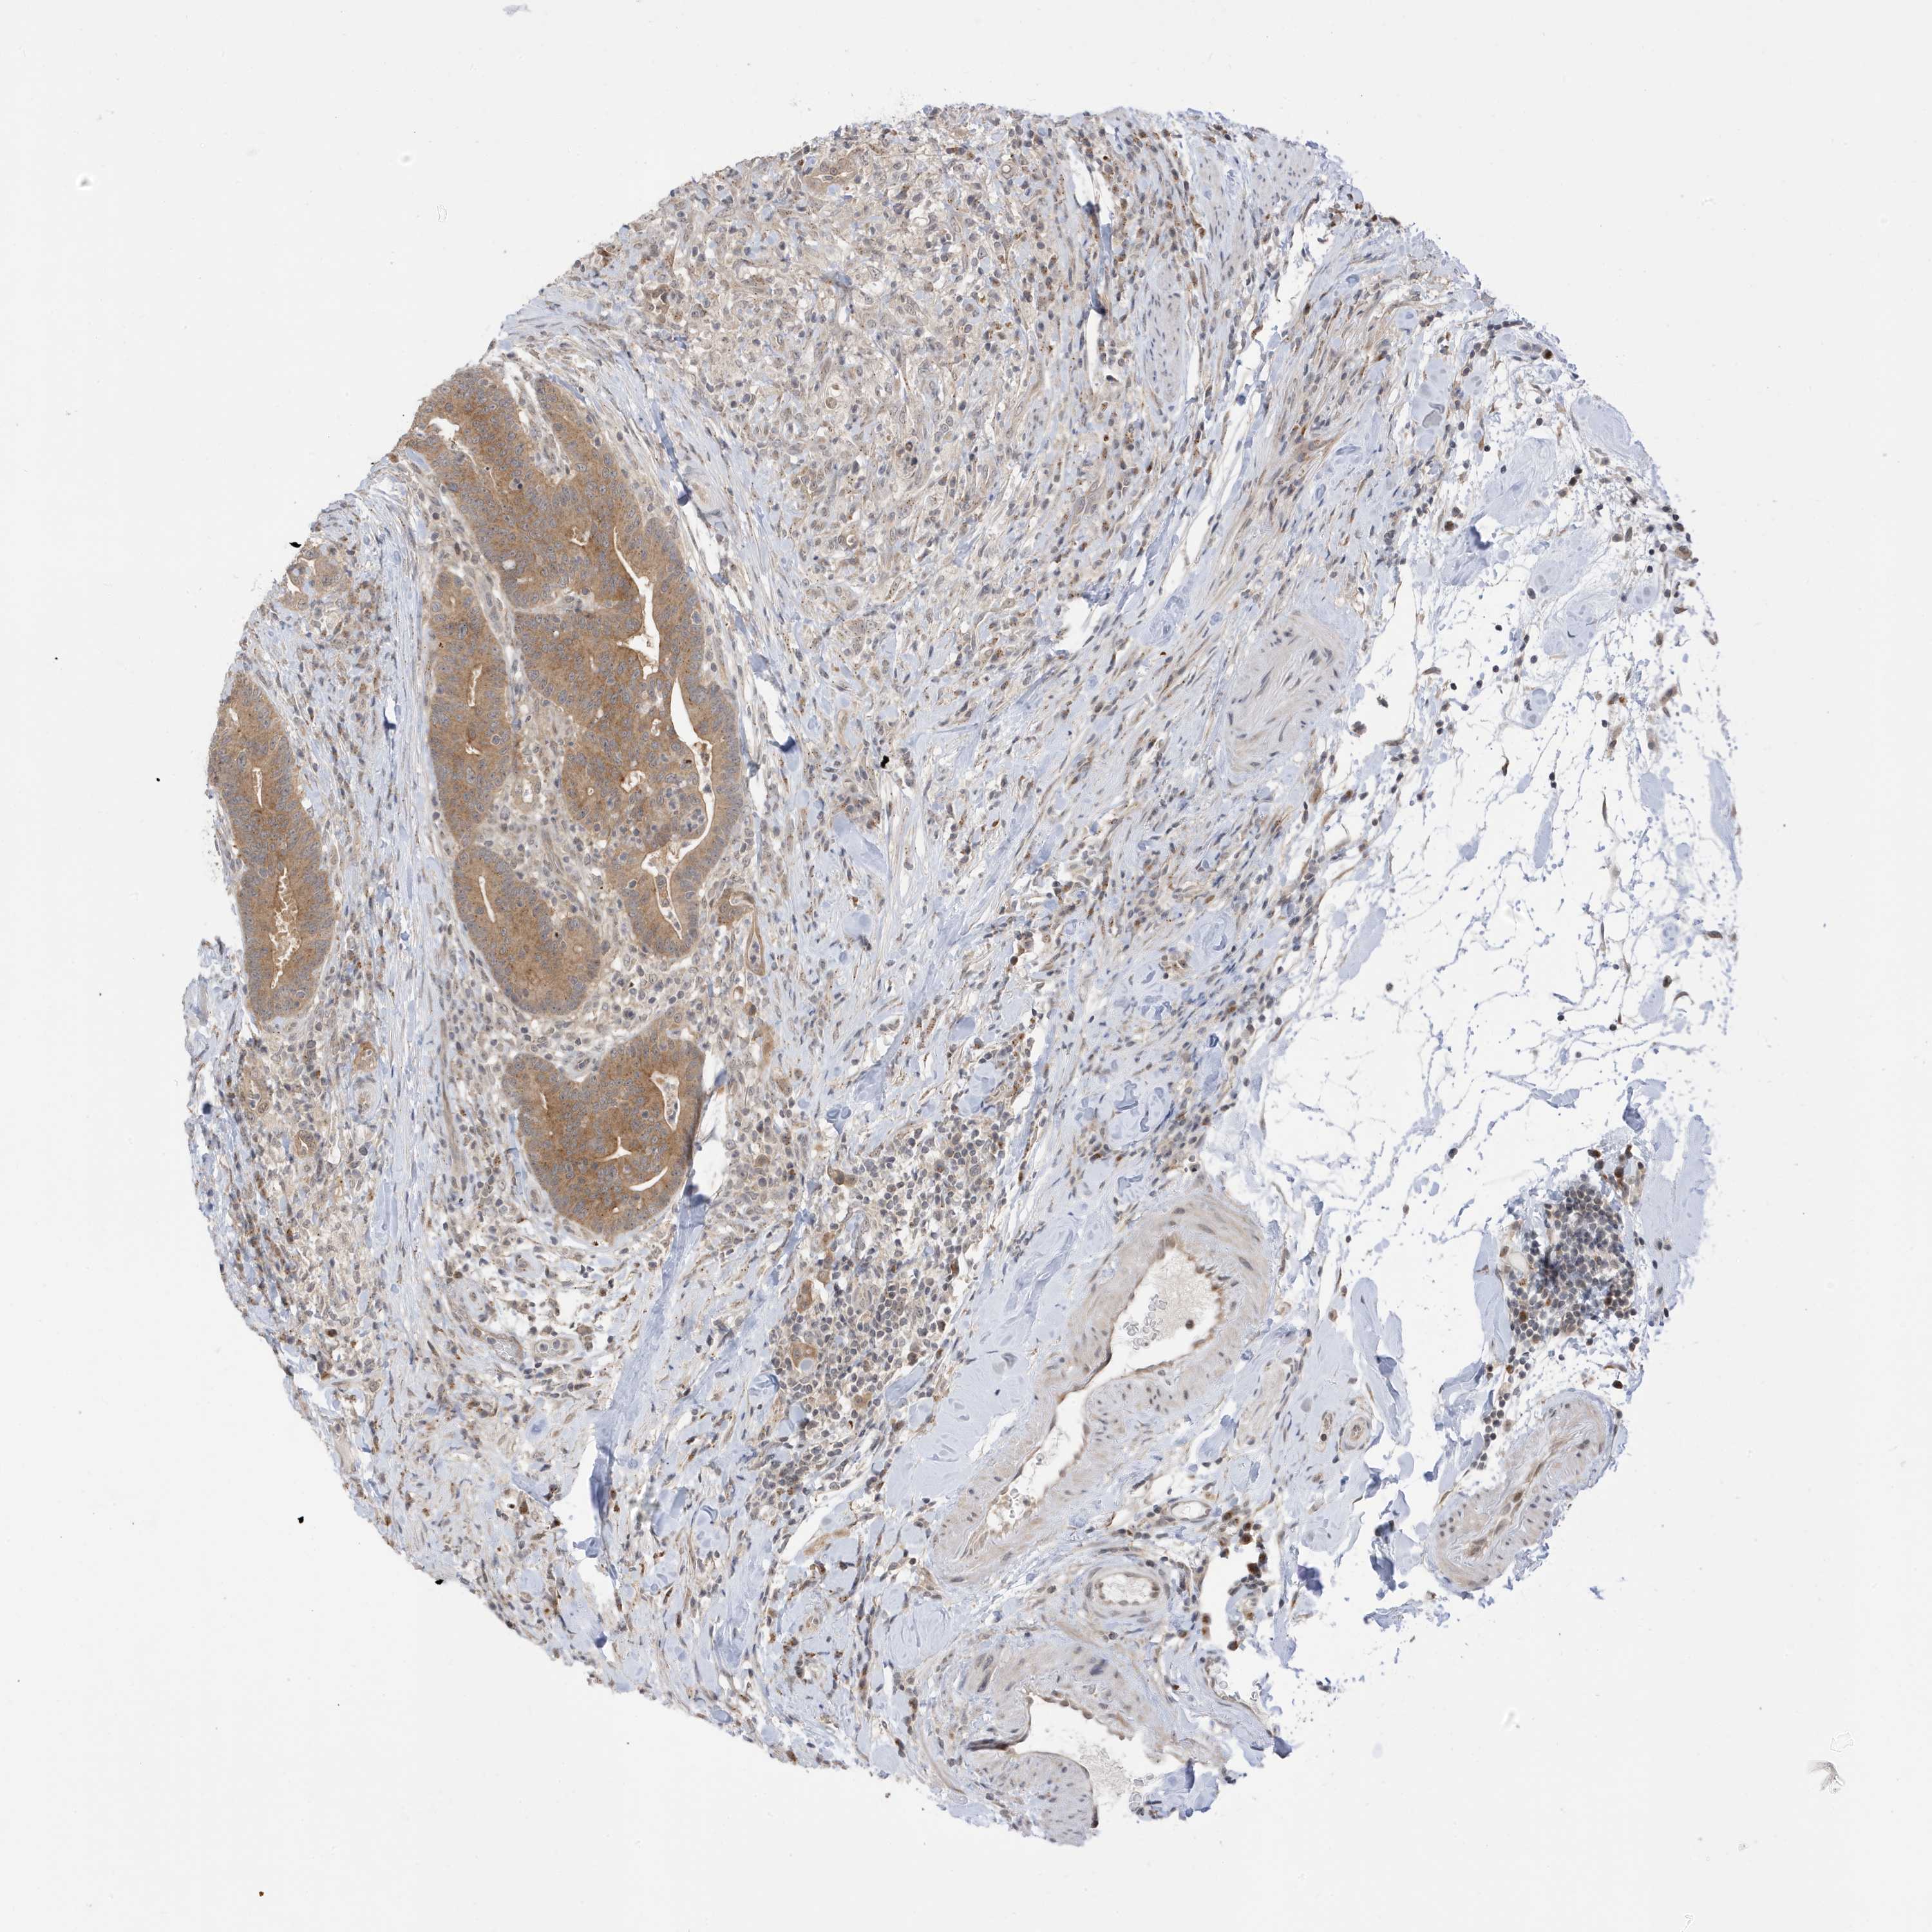

CANCER COLORECTAL CANCER Show tissue menu

Colorectal cancer

Human cancer

Colon adenocarcinoma